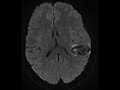

Hemorrhagic Arteriovenous Malformation

These images demonstrate hemorrhage in the left parieto-temporal region best demonstrated on the susceptibility weighted images. Coronal MRV post-contrast images show a small nidus compatible with an arteriovenous malformation. The differential diagnosis on the CT where only hemorrhage was identified included hemorrhagic venous infarction in this young patient. In an elderly patient, the differential for lobar hemorrhage would include amyloid angiopathy. Subsequent catheter angiography showed the nidus to be supplied by two enlarged cortical branches of the superior division of the left middle cerebral artery.